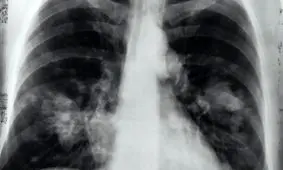

تحقیقات محققان چینی نشان میدهد ۹۰ درصد افراد بهبود یافته از کووید ۱۹ از آسیب ریوی شدید رنج میبرند.